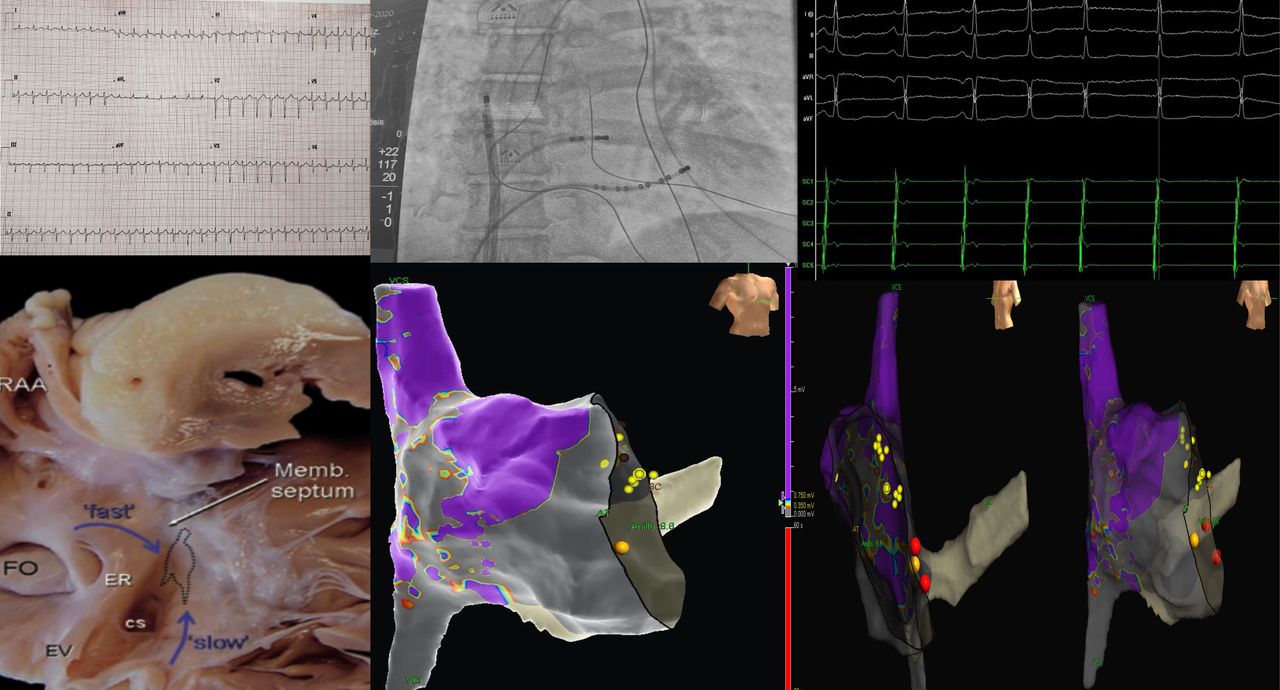

Realicé mi formación como médico general en la Universidad Autónoma de Veracruz Villa Rica, posteriormente la especialidad en medicina interna durante dos años en centro medico nacional Adolfo Ruiz Cortinez UMAE 14 en Veracruz, recibiendo en el primer año el reconocimiento por excelencia académica y en el segundo año reconocimiento al mejor promedio de mi generación. Realicé la subespecialidad en Cardiología clínica en el Centro Médico Nacional “La Raza”, en la Ciudad de México siendo jefe de residentes en el último año de la residencia médica, durante el tiempo la sede recibió el premio a la mejor cede de formadores de cardiología 2012-2013 premio otorgado por Dr. Enrique Graube (en ese entonces Director de medicina UNAM). Entre mis actividades asistenciales y conferencias, he presentado trabajos libres a nivel internacional (congreso de falla cardiaca lisboa 2013, Congreso mundial de cardiologia 2016, 2018 en AHA) ganador del premio internacional “la imagen más bella en cardiología, sociedad europea cardiologia España 2013”, así mismo presentación de más de 35 articulos publicados en revistas indexadas, soy miembro de la sociedad mexicana de cardiología no. 2076, asociación mexicana de cardiología, Fellow in training de la American collegue of cardiology capítulo México. Miembro de la sociedad europea de cardiología ESC ID 509395. Médico adscrito en el centro médico nacional la Raza, fui profesor adjunto del curso de cardiología en el mismo centro y sindal en el exámen de certificación de cardiología clínica de la sociedad mexicana de cardiología. Desde el 2016-2018 realicé curso de alta especialidad en electrofisiología cardiaca y estimulación cardiaca , realizando cursos fuera del país para especialización en técnicas avanzadas de ablación de arritmias, actualmente me encuentro realizando en el segundo año de la maestría en Dirección y Gestión de Instituciones de salud y Especialidad en Gestión de la Salud y Bienestar Corporativo

• Arritmias